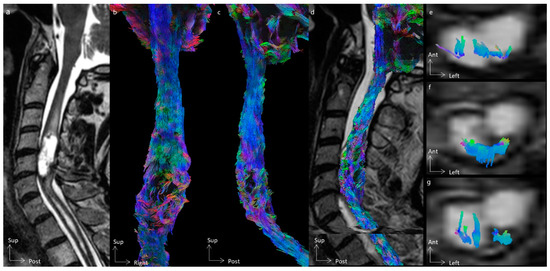

3.2. Tractography Rendering

4.2. The Added Value of Tractography